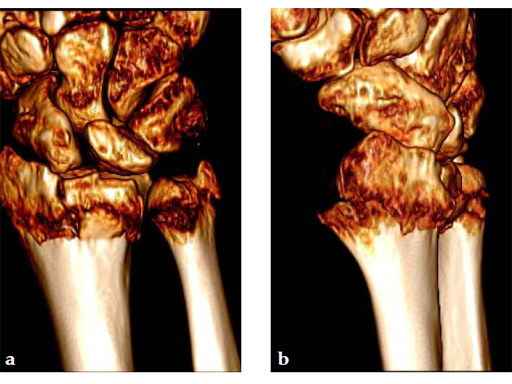

Case 2: A 44-year-old man sustained polytrauma following a car accident. Among his injuries was a distal radial fracture, Mller AO Classification 23-C1.

Case provided by Vitezslav Ruber, Brno, Czech Republic